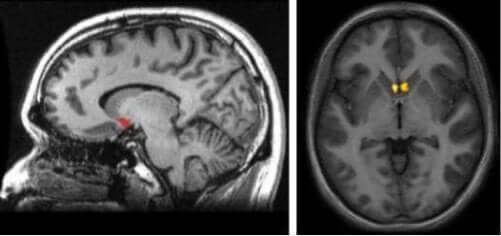

Nu stiller du måske dig selv spørgsmålet, hvor denne hjernestruktur er lokaliseret. For at give dig en idé om det, skal du visualisere det subkortikale område (under cortex) lige ved forbindelsespunktet mellem caudate nucleus, putamen og septum.

Et af de mest signifikante aspekter ved nucleus accumbens er dets lokalisering, da det er en del af den dopaminergiske sti i hjernen. Det er den såkaldte mesolimbiske sti. Den står for at stimulere dig, når end din hjerne mener, du oplever en behagelig og tilfredsstillende oplevelse.